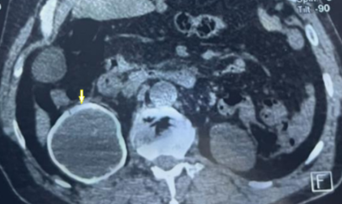

Primary Alveolar Echinococcosis of the Kidney…